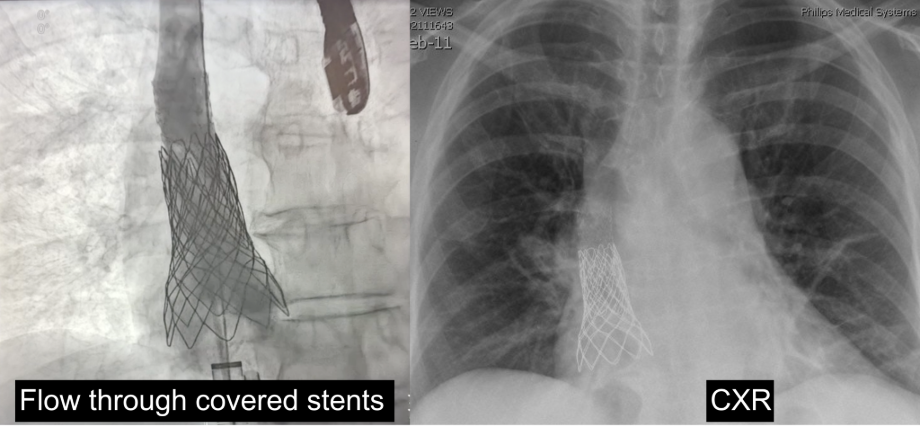

Ing explained they would first need to close the ASD by implanting a large, covered stent anchored in the superior vena cava and extending down to the ASD. But it was not as simple as just plugging up a hole. They needed to cover the hole but also allow blood from the anomalous pulmonary veins to return properly to the left atrium.

To avoid this problem, Ing inflated two high-pressure balloons in the middle of two pulmonary veins. Then he implanted the covered stent under low pressure. Because of the two different states of pressure, the two high-pressure balloons prevented the stent from encroaching the opening of the veins. This allowed the stent to mold to the shape of the two balloons.

“In the end, we were able to successfully close the hole in her heart and allow the two middle pulmonary veins that were in question (plus the lowest pulmonary vein) to get flow to the left atrium without any obstruction,” Ing shared.